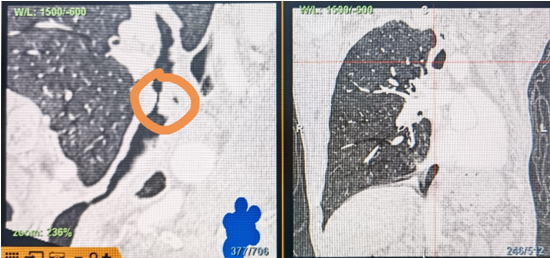

時(shí)間就是生命!了解患者病情后,歐陽海峰立刻啟動氣道梗阻緊急救治通道,協(xié)調(diào)院前轉(zhuǎn)運(yùn),急診快速入院流程。凌晨患者入院胸部CT顯示,現(xiàn)存唯一的呼吸通道在右主支氣管處,狹窄處僅約3毫米,患者命懸一線!

運(yùn)用呼吸介入技術(shù),軟硬鏡結(jié)合快速開通氣道,是患者目前唯一可行的治療方案,手術(shù)刻不容緩!但存在麻醉后氣道完全塌陷閉合、大出血、窒息等巨大風(fēng)險(xiǎn)?;颊叽饲敖舆B轉(zhuǎn)診3家醫(yī)院,均建議保守支持治療或轉(zhuǎn)院。歐陽海峰詳細(xì)了解患者病史,全面評估影像檢查結(jié)果后,決定盡快進(jìn)行手術(shù),組織醫(yī)護(hù)團(tuán)隊(duì)對患者進(jìn)行持續(xù)密切監(jiān)測,充分保障其術(shù)前安全。